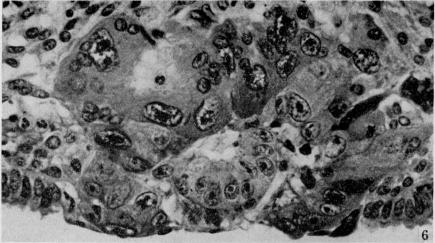

On the development of the amnion and exoccelomic membrane in the previllous human ovum.

Yale J Biol Med. 1945 Dec;18(2):107-15.